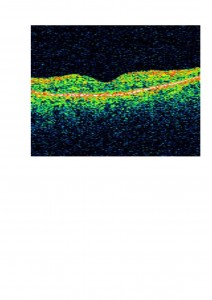

En este paciente decidimos tratar el edema macular cistoide previo a la cirugía de cataratas con acetazolamida oral debido a que muy probablemente iba a empeorar tras la cirugía. En la OCT os mostramos cómo disminuyó el edema:

Efectivamente, 1 mes después de la cirugía de cataratas el edema empeoró en ambos ojos:

Volvimos a aumentar la dosis de acetazolamida oral asociada a antinflamatorios no esteroieos tópicos (diclofenaco colirio) y el edema disminuyó:

Después de varios meses, la acetazolamida dejó de hacer efecto y el edema recidivó parcialmente. Suspendimos el tratamiento pero el paciente mantiene, 2 años después, una agudeza visual de 0,5 en ambos ojos y consideramos que la acetazolamida nos ayudó en el control perioperatorio del edema.